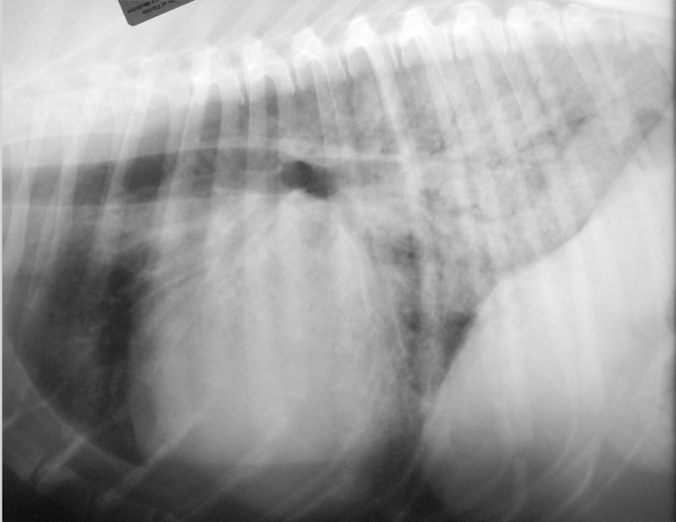

What is the likely condition? What are the arrows pointing to?

Aspiration pneumonia (bc right middle)

red: air bronchogram

blue: border effacement

yellow: lobar sign

What condition is this showing in a dog? How would it differ in a cat?

Cardiogenic edema (perihilar distribution)

Cat: would look patchy and mulitfocal anywhere (see image)

General condition?

Atelectasis

note the mediastinal/cardiac shift to the right and the soft tissue opacity of right middle lung lobe

What condition?

Atelectasis secondary to pneumothorax

note: retraction of lung lobes from thoracic wall and soft tissue opacity of left and right middle lung lobe